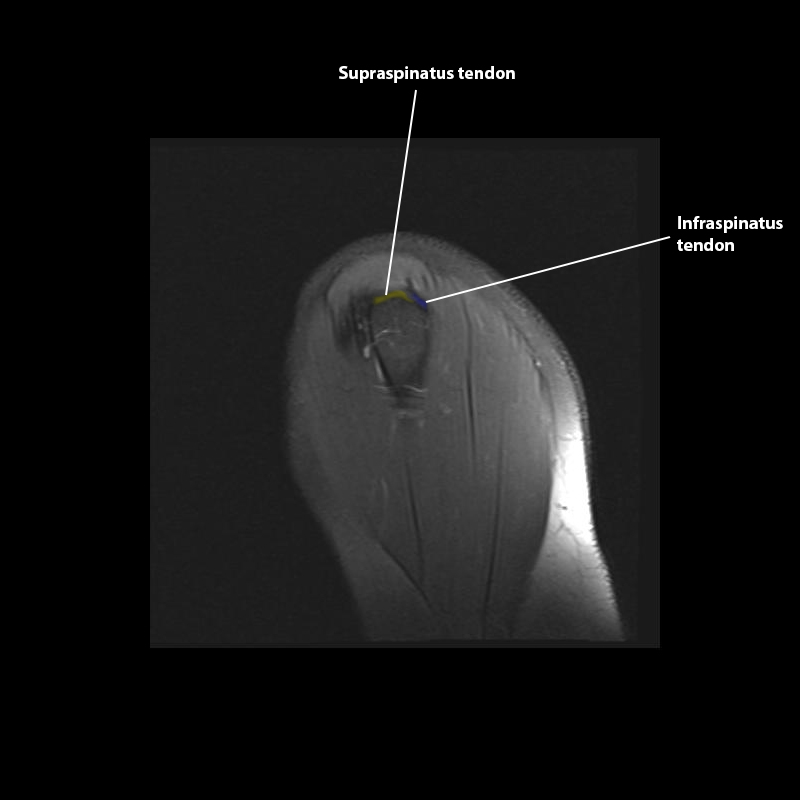

Shoulder MRI Anatomy